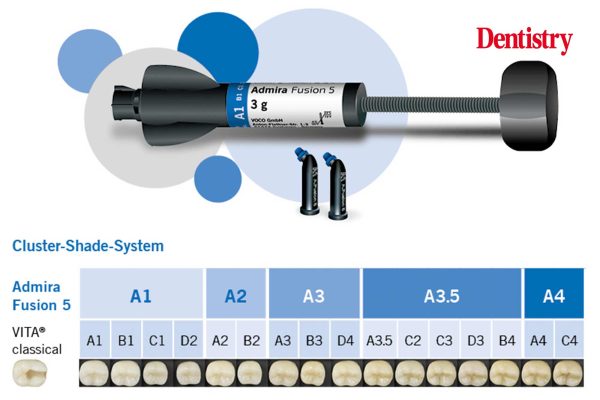

Simple restoration creates illusion of depth

Elaine Mo describes restoring a carious molar with durable composite resin, overcoming the challenge of naturally deep fissures. Direct composite…

Caries management with nano-hybrid science

Vishaal Shah presents a case in which the challenges of treating caries were overcome with skill, attention to detail and…